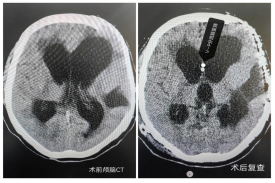

患者情况与手术背景:患者为红原县60岁女性,因脑外伤接受去骨瓣减压术后出现交通性脑积水,长期昏迷且辗转多家医院治疗效果不佳。经阿坝州人民医院神经外科团队详细评估,并与2025年“同心·共铸中国心”阿坝公益行动活动中的北京神经外科专家团队会诊后,决定采用腹腔镜下V-P分流术进行治疗。

手术由神经外科文家智副主任医师团队与普外科石汶副主任医师团队协作完成:神经外科精准定位颅骨钻孔,将分流管脑室端置入脑室,并沿皮下隧道引至右上腹壁。普外科在腹腔镜辅助下,通过两个1厘米微小切口,将分流管腹腔端精准放置于盆腔子宫直肠隐窝,减少大网膜包裹风险。手术全程顺利,患者出血极少,生命体征平稳,术后转入神经外科密切监护。